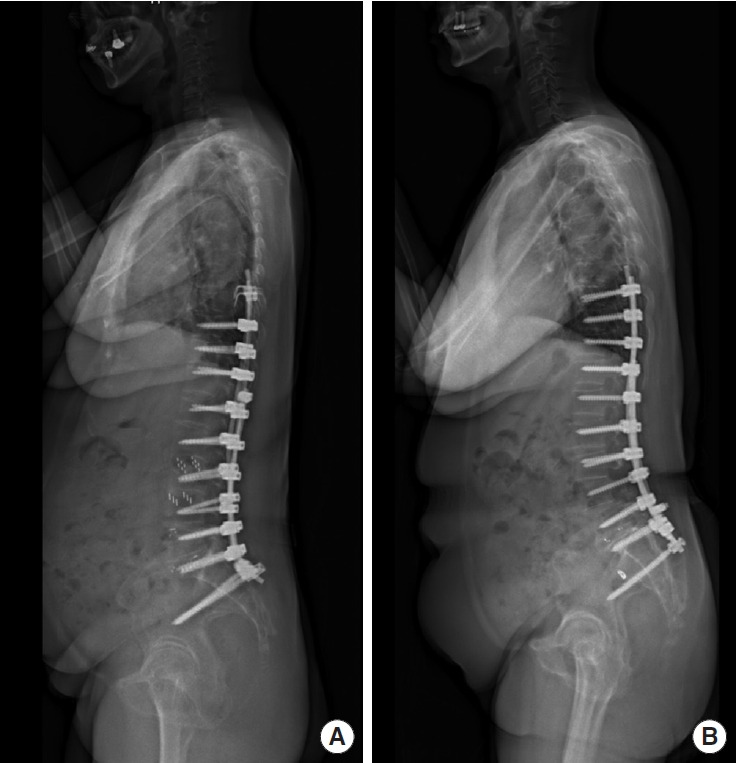

Abstract Image